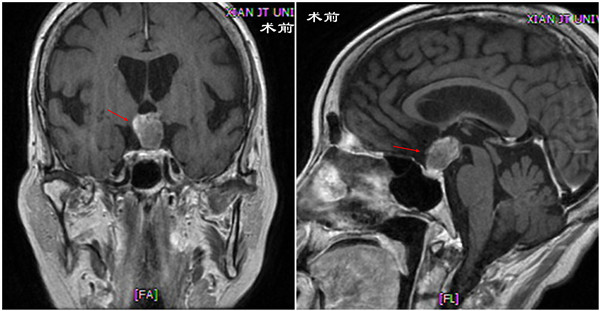

这是一名68岁的女性患者,以“视力下降2年,头痛、恶心、呕吐2月余”之主诉就诊于我院神经外科。患者近两年视力下降,2个多月前无明确原因出现头痛伴恶心、呕吐,在当地医院做颅脑CT发现“鞍区占位性病变”,MRI报告“鞍区混合信号肿物,考虑垂体瘤伴出血可能”,为进一步诊治来我院,以“鞍区肿物”之诊断收住院。患者5年前有过左侧眼底出血。入院时查体:神志清楚,语言清晰,右眼视力0.15,左眼眼前指动,眼底检查可见右侧视盘苍白,左侧无法窥入。我院MRI增强扫描报告“颅咽管瘤”。眼科会诊明确合并双侧老年性白内障。激素水平检查提示其垂体功能低下,在内分泌科指导下进行激素替代治疗,纠正甲状腺激素水平和皮质醇水平。

术前 冠状位(左) 术前矢状位(右)

在屈建强主任的支持下,经过充分细致的准备,于2021年11月22日,与麻醉手术科刘鹏斌教授、赵梦溪、熊哲、杨欢欢等合作,吕健主任医师、王举波主治医师、肖俊医师、宋琴等在全麻下为患者施行了内镜经鼻扩大颅底入路鞍区肿瘤切除术。手术中,应用神经内镜,经双侧鼻腔抵达颅底,磨除鞍底、鞍结节和蝶骨平台后部骨质,剪开硬脑膜,见肿瘤位于视交叉后、第三脑室底与垂体之间,沿垂体柄全长生长,上端与视交叉及第三脑室底部附着紧密。肿瘤呈实体性,质地韧硬不均匀,广泛钙化,先瘤内减容,再分离包膜,肿瘤次全切除,用自体脂肪、人工硬膜、带蒂鼻中隔黏膜瓣重建颅底。手术顺利,麻醉满意,出血不多,未输血。术后患者恢复顺利,有多饮多尿,但数日后恢复正常,无脑脊液鼻漏,已出院。组织病理学检查证实了颅咽管瘤之诊断。